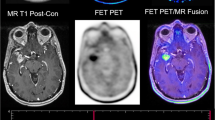

Gallium-68 DOTATOC (DOTA-[Tyr3]-Octreotide) is one specific radiopharmaceutical which is highly sensitive to somatostatin-receptors subtype 2 (SSR2) that is expressed in neuroendocrine tumors and in the brain tumor like meningioma (Fig. 1.2). Other than the FDG and Ga-68 DOTATOC, research has been done in amino acid tracers for PET imaging of brain tumors (Fig. 1.3). The novel tracers which have been employed include positron labeled methionine, thymidine, tyrosine, choline and fluoromisonidazole (Basu and Alavi, 2009). One of the key advantages of these new radiotracers over FDG is a significant reduction in background activity from gray matter which allows the detection of small tumors with high precision (Basu and Alavi, 2009). The emphasis has also being placed on investigating amino acid tracers which are sensitive to recurrent tumor particularly the low-grade ones because they are difficult to be detected. O-(2-[18F]fluoroethyl)-L-tyrosine (FET) is a novel amino acid PET tracer (Fig. 1.3) that has been shown to have better differentiation capabilities for tumor tissue from inflammation. 18F-FET is being investigated for monitoring post therapeutics of Squamous Cell Carcinoma (SCC) because the tumor tissue reaction can now be specifically detected by FET, in which the surrounding inflammatory tissue will not show any uptake (Pauleit et al., 2006).

Patient with a high grade Glioma tumor showing T1w post contrast (a) enhancing margins with the central area of necrosis in the tumor, T2w image (b) confirming the findings. The combined PET-CT using FET tracer (c) shows the tumor clearly with infiltrations to the cerebral cortex and infiltration to the contralateral hemisphere. The bottom row shows the PET image in axial (d), coronal (e) and sagittal (f) plane confirming infiltration to contralateral hemisphere in the coronal plane (arrow)